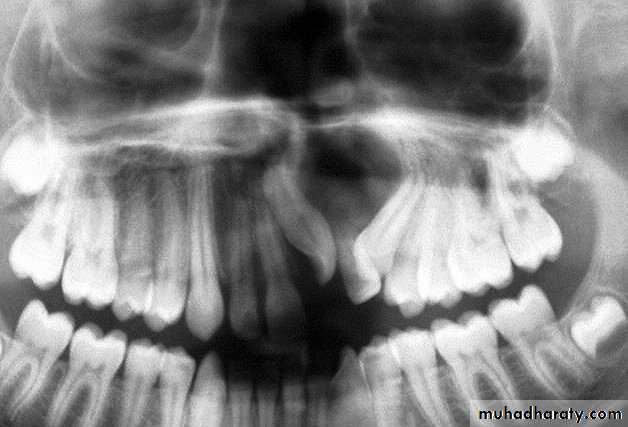

3. Dentigerous cysts:These cysts develop after deposition of enamel and are probable,result of degenerative changes in the reduced enamel-formingepithelium. The fact that the epithelium of a dentigerous cyst isattached to the neck of the tooth is fairly strong evidence that in mostcases the cyst is formed by the enamel organ and not independently of it A dentigerous cyst contain a crown of un erupted tooth or dentalanomaly such as odontoma. Enlarge D.cysts can cause a markeddisplacement of teeth. Pressure of accumulated fluid usually displacesthe tooth in an apical direction.

D.cysts may found any where in the mandible or the maxilla butare more frequently located at the angle of the jaw. The cuspid regionsmaxillary third molar areas. Treatment by complete surgical enucleation